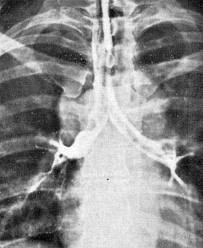

Диагноз устанавливается на основании анамнеза, клинических проявлений, данных обзорной рентгенографии, томографии, трахеобронхоскопии, спирографии, бронхографии, а также лабораторных исследований крови.

Медицинские процедуры, проводимые при заболевании бронхостеноз: Бронхоскопия, Бронхография, Рентгенография грудной клетки, Компьютерная томография, Спирография при записи на автоматических аппаратах, Клинический анализ крови, Исследование газов крови

Стеноз бронхов в зависимости от степени его выраженности и анатомических особенностей может сопровождаться развитием частичного или полного ателектаза соответствующего отдела легкого, а при наличии клапанного механизма с затрудненным выдохом — к развитию эмфиземы соответствующих отделов легкого.